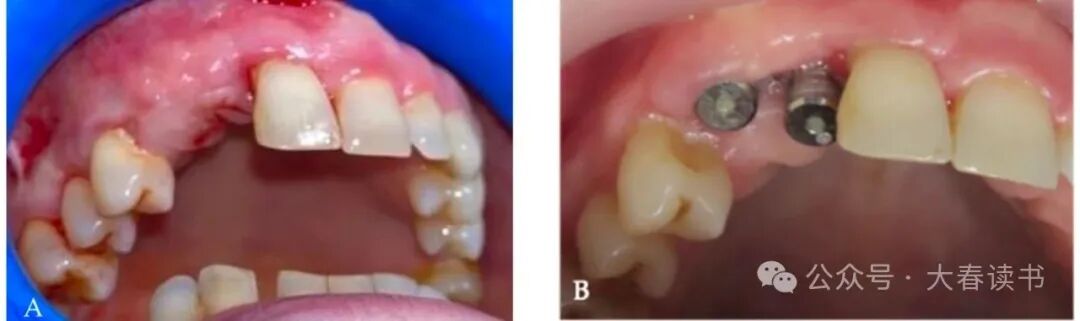

Figure 8: Suturing to close the wound.

Figure 12: Intraoral view: a, Gingival status before placing the healing abutment. b, Placement of the healing abutment.